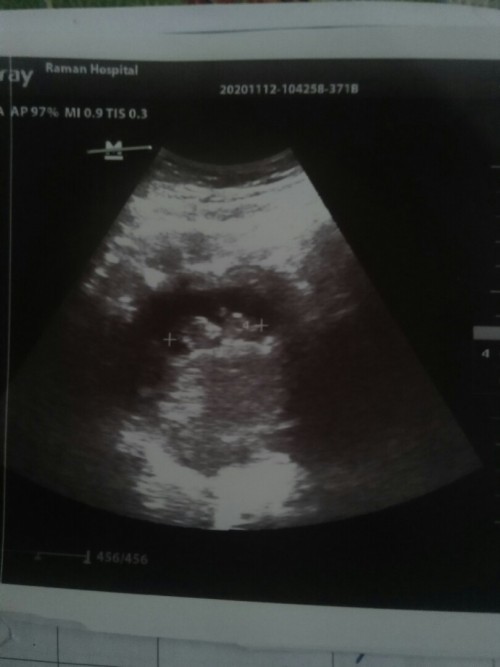

ค่ะ ตอนนี้ไม่รู้ว่าหนูน้อยเพศอะไร แต่ก็จะติดตามคุณแม่ศิวพรรอดูว่าเราจะได้ลูกเพศอะไรกันนะคะ